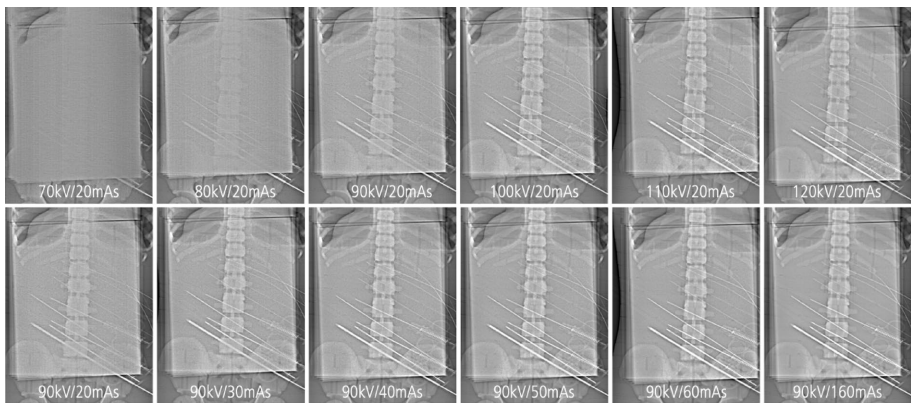

为解决CT引导介入术中实时可视化需求与辐射暴露的矛盾,本研究系统评估了利用CT定位像(scout view)实现类透视成像的可行性。研究发现,通过优化扫描参数(如≥80kVp/≥60mAs),可在常规至超重患者中清晰显示介入器械(如活检针、导丝),为对比剂注射和器械操作提供实时监控,显著降低辐射剂量。该技术为CT介入提供了新型辅助工具。